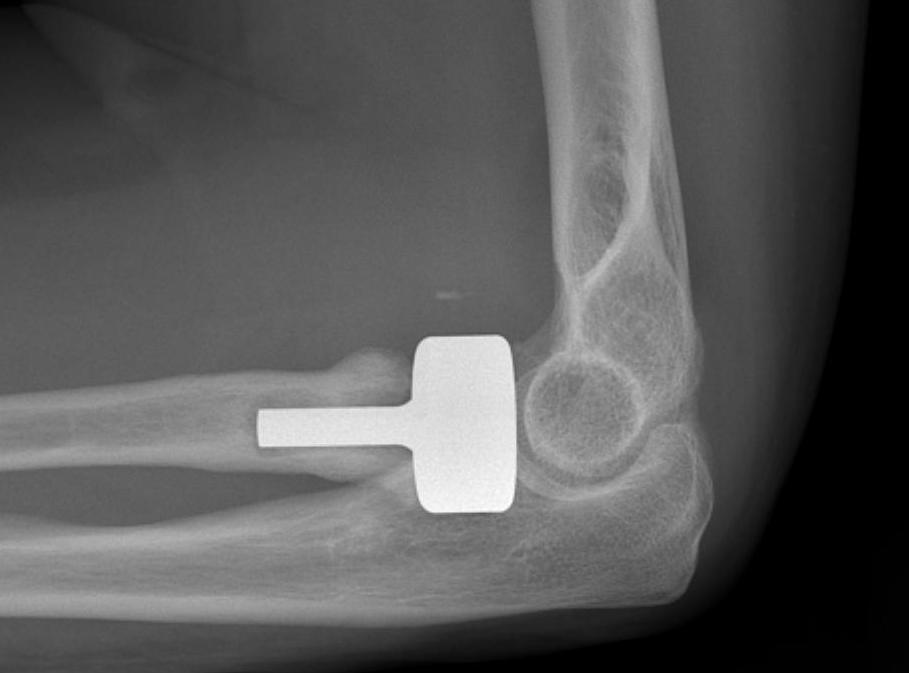

Overstuffing

| Lesser sigmoid notch | Symmetry of ulnohumeral joint |

|---|---|

|

Radial head shoulder articulate with lesser notch

Ensure no gapping of lateral ulnohumeral joint |

- cadaveric study

- increased medial ulno-humeral joint line gapping with overlengthening of 6 or 8 mm

- increased lateral ulno-humeral joint line gapping with overlengthening of 2 mm